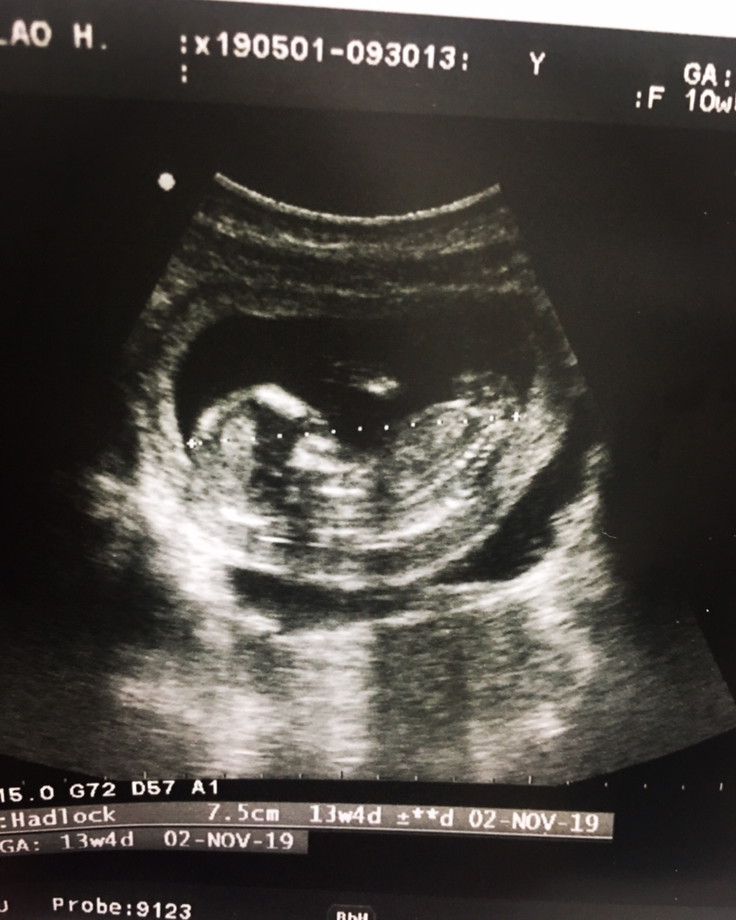

ซาวตอน13สัปดาห์ จนตอนนี้20สัปดาห์แล้วยังไม่รู้เพศเลย

14 ธันวาค่ะ น้องเป็น ผญ จากการตรวจนิฟตี้ #รูปตอน12วีค